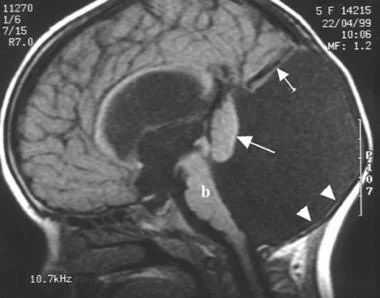

По данным МРТ было выделено несколько разновидностей синдрома Денди-Уокера:

- Классический тип аномалии — задняя черепная ямка расширена, четвертый желудочек кистозно изменен, червь мозжечка частично или полностью недоразвит, полушария его гипоплазированы, а намет находится выше, чем в норме, желудочковая система не сообщается с подпаутинным пространством, часто наблюдаются мозговые кисты и отсутствие мозолистого тела, практически у всех пациентов есть гидроцефалия, возможно сдавление стволовых структур. Порок проявляется клинически уже с рождения и имеет неблагоприятный прогноз.

- Вариант Денди-Уокера — морфологические признаки выражены меньше, чем при классической форме, гипоплазирован нижний отдел червя мозжечка, желудочки сообщаются с кистой и ликворными пространствами, обеспечивая отток ликвора, поэтому гидроцефалия наблюдается редко. Задняя черепная ямка имеет нормальные размеры, стволовые структуры не сдавливаются.

- Киста кармана Блейка — расширение желудочковой системы с гидроцефальным синдромом, киста расположена под или за мозжечком, червь развит относительно хорошо. Четвертый желудочек расширен, но не сообщается с затылочной ликворной цистерной.

- Mega cisterna magna — вариант очагового расширения подпаутинного пространства в задней и нижней частях задней ямки черепа с увеличением объема затылочной цистерны, которая сообщается с четвертым желудочком и субарахноидальным пространством.

- МРТ для определения анатомических особенностей четвертого желудочка мозга;

- МРТ головного мозга. Магнитно-резонансная томография в сагиттальной и аксиллярной проекции демонстрирует расширение четвертого желудочка, грубые нарушения развития мозжечка, другие структурные аномалии.